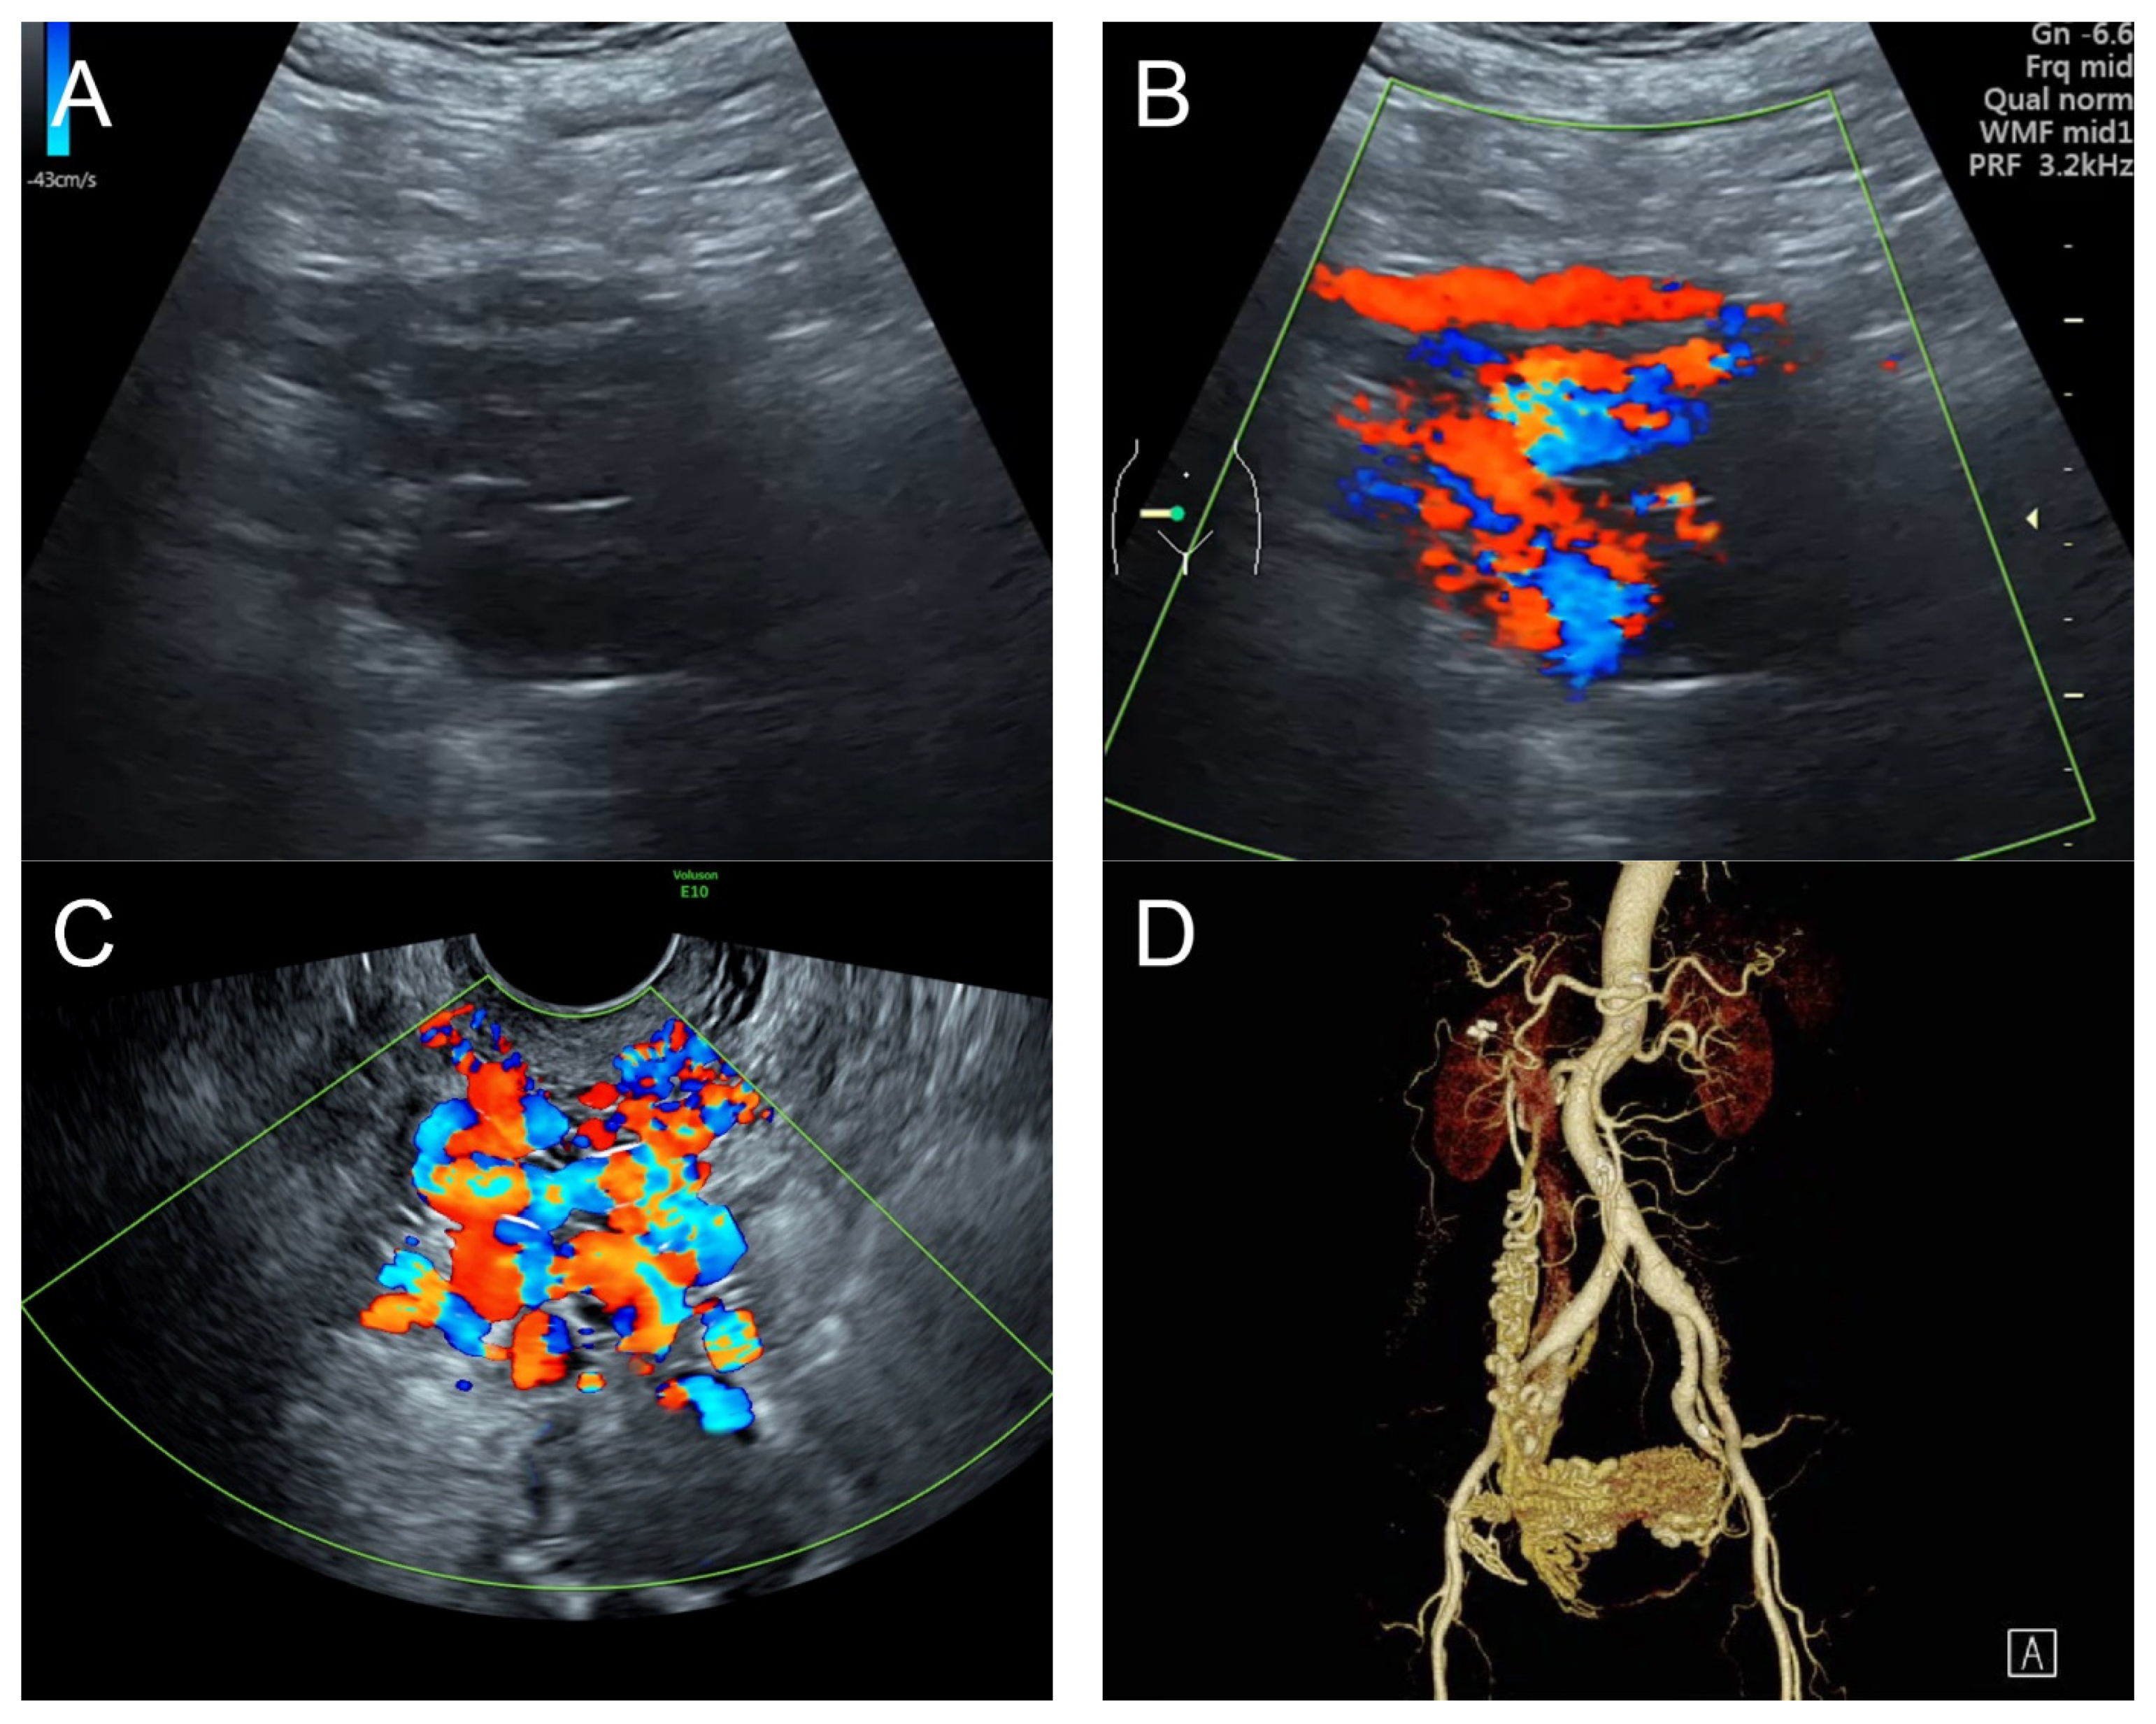

Figure 6.

(A) Transvaginal ultrasound: sagittal scan of the uterus showed heterogeneous echoes of the myometrium; a dilated arcuate artery at the posterior wall; several small anechoic/hypoechoic spongy structures within the myometrium, mainly at the anterior wall; no other specific lesions of the uterus. The endometrium appears normal. (B) Cross-sectional scan of the fundus showed several small anechoic/hypoechoic tubular structures or a spaghetti-like appearance throughout the myometrium. (C) Color flow mapping showed hyper-vascular areas in the myometrium, without well-defined lesion borders; multidirectional flow mainly localized at the anterior wall. The main differential diagnosis was adenomyosis or gestational trophoblastic disease. (D) Abdominal CTA revealed hypervascularity and tortuous arterial anatomy enhancing dilated vessels of the uterus, with bilateral uterine arteries as the feeding arteries, confirming uterine AVM.